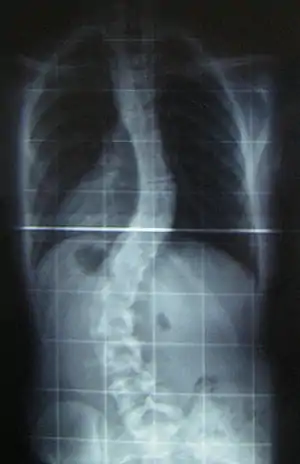

When scoliosis is suspected, weight-bearing, full-spine AP/coronal (front-back view) and lateral/sagittal (side view) X-rays are usually taken to assess the scoliosis curves and the kyphosis and lordosis, as these can also be affected in individuals with scoliosis. Full-length standing spine X-rays are the standard method for evaluating the severity and progression of scoliosis, and whether it is congenital or idiopathic in nature. In growing individuals, serial radiographs are obtained at 3- to 12-month intervals to follow curve progression, and, in some instances, MRI investigation is warranted to look at the spinal cord.[76] An average scoliosis patient has been in contact with around 50–300 mGy of radiation due to these radiographs during this time period.[77]

The standard method for assessing the curvature quantitatively is measuring the Cobb angle, which is the angle between two lines, drawn perpendicular to the upper endplate of the uppermost vertebra involved and the lower endplate of the lowest vertebra involved. For people with two curves, Cobb angles are followed for both curves. In some people, lateral-bending X-rays are obtained to assess the flexibility of the curves or the primary and compensatory curves.